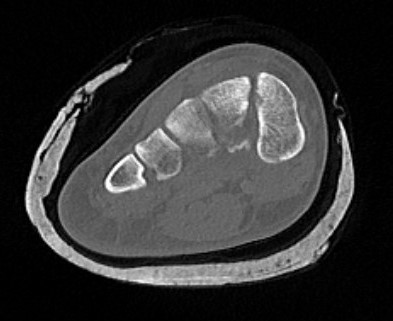

CT

Fleck sign

Fleck sign with inter-cuneiform widening

Dorsal subluxation of the metatarsal